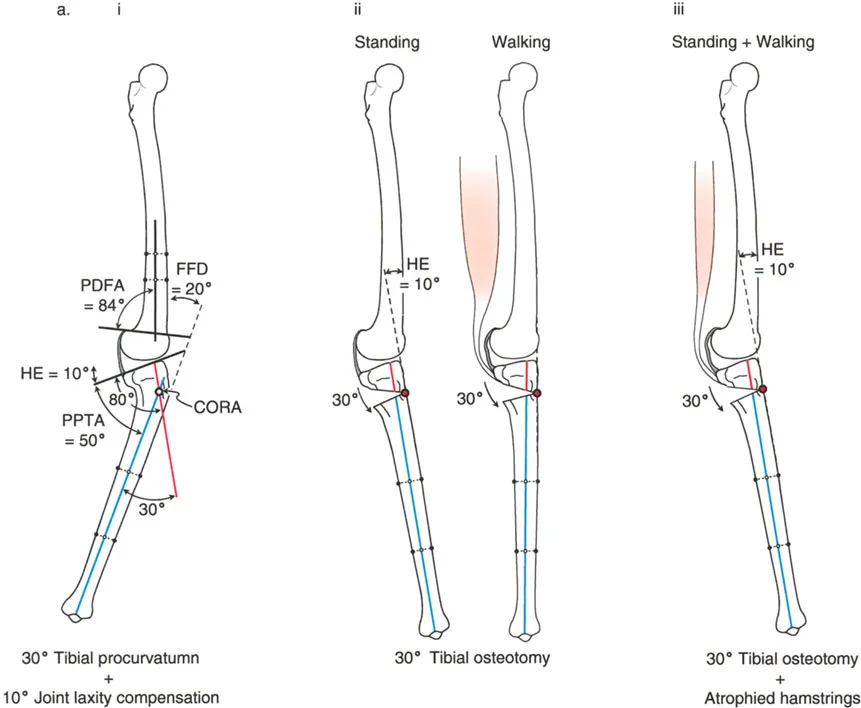

- تحدُّد حركة الركبة (Flexion Deformity - FFD): عدم القدرة على مد الركبة بالكامل، بحيث تظل الركبة في وضعية انثناء جزئي حتى عند محاولة فردها. يمكن أن يكون هذا ناتجًا عن تشوهات عظمية (مثل تقوس عظم الفخذ أو الساق للأمام) أو تقلصات في الأنسجة الرخوة (الأوتار والعضلات).

- الركبة الارتدادية (Recurvatum Deformity - Hyperextension): تمدد الركبة بشكل مفرط للخلف (فرط البسط)، أي تجاوز نقطة الاستقامة الطبيعية. يمكن أن يكون هذا ناتجًا عن ضعف العضلات (خاصة أوتار الركبة) أو تشوهات عظمية.

تصحيح تحدد حركة الركبة (Flexion Deformity - FFD)

تحدُّد حركة الركبة هو عدم القدرة على مد الركبة بالكامل. يمكن أن يكون سببه عظميًا أو ناتجًا عن تقلص في الأنسجة الرخوة.

- التشخيص الدقيق: يجب تحديد ما إذا كان تحدد الحركة ناتجًا عن تشوه عظمي (تقوس أمامي في الفخذ أو الساق) أو تقلص في الأنسجة الرخوة (الأوتار الخلفية، محفظة المفصل).

- قطع العظم التمديدي (Extension Osteotomy):

- إذا كان التشوه عظميًا، يتم إجراء قطع عظم تمديدي في عظم الفخذ أو الساق لتصحيح التقوس.

- الأستاذ الدكتور محمد هطيف يؤكد على أهمية عدم تصحيح الساق بأكثر من 90 درجة PPTA لتجنب فقدان الميل الخلفي الطبيعي للساق.

تصحيح الركبة الارتدادية (Recurvatum Deformity - Hyperextension)

الركبة الارتدادية هي فرط البسط في الركبة. غالبًا ما تكون غير مصحوبة بأعراض في الأشخاص ذوي العضلات السليمة، ولكنها قد تسبب مشاكل في حالات ضعف العضلات أو التشوهات العظمية.

- التشخيص: يجب تحديد ما إذا كانت الارتدادية عظمية (تقوس خلفي في الفخذ أو الساق) أو ناتجة عن رخاوة في الأنسجة الرخوة أو ضعف عضلي.

- قطع العظم الانثنائي (Flexion Osteotomy):

- إذا كان التشوه عظميًا (تقوس خلفي)، يتم إجراء قطع عظم انثنائي في عظم الفخذ أو الساق لتصحيح الارتدادية.

- الأستاذ الدكتور محمد هطيف يشدد على أهمية عدم استخدام قطع عظم الفخذ الانثنائي لتصحيح ارتدادية الساق، والعكس صحيح، لتجنب الانزلاق الخلفي أو الأمامي للركبة.

- اعتبارات خاصة: في المرضى الذين يعانون من ضعف عضلي (مثل شلل الأطفال)، قد يحتاج التصحيح إلى فرط تصحيح بسيط (overcorrection) إلى وضعية انثناء لضمان ثبات الركبة ومنع فرط البسط غير المتحكم فيه.